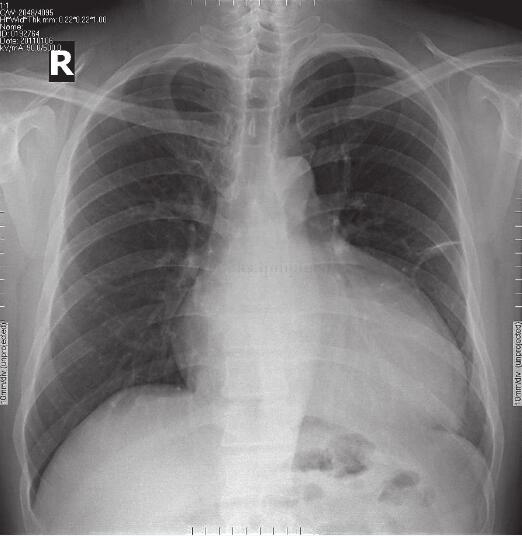

胸片:心影增大(图1-4-1)。

图1-4-1 治疗前胸片